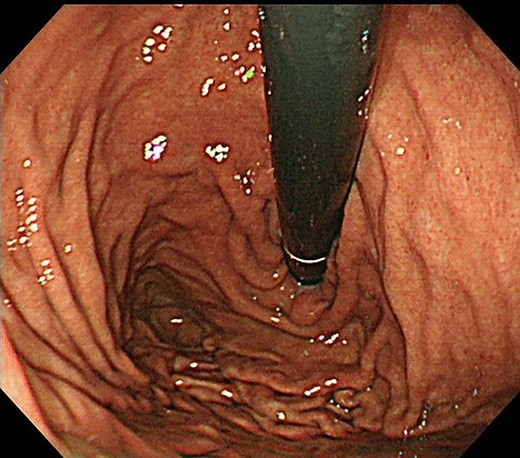

Contrast-enhanced computed tomography revealed a giant irregular mass (45 × 35 mm) in the abdominal wall (Fig. 2). No other intra-abdominal neoplasm were present; however, an irregular lung mass measuring 50 mm in size in the S10 region of the right lobe and a mass measuring 12 mm in size in the S1/2 region of the left lobe were found (Fig. 3). Total gastrointestinal endoscopy, including capsule endoscopy, revealed no neoplasm in the intestinal tract (Fig. 4a–c).